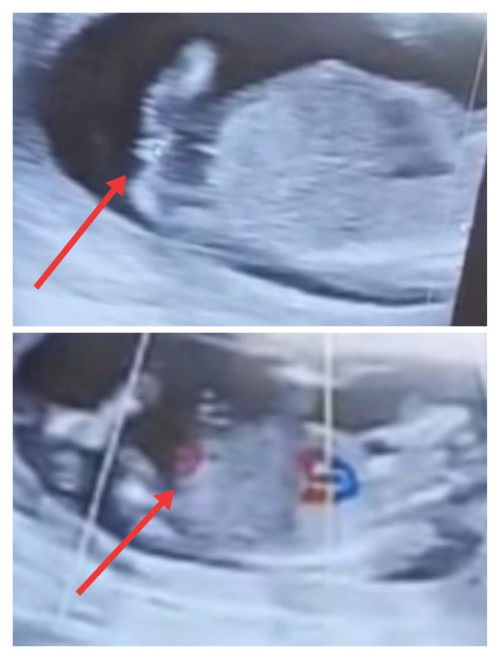

Jenis kelamin

Selamat pagi bunda semua.. Kira² kalau foto usg ini jenis kelamin cowok atau cewek ya? Saya penasaran bun soalnya itu pas usg 14 w.. dan dokternya belum mastiin itu cwek atau cwok, .. Dan ini belum usg lagi nunggu jadwal.. Sehat² untuk bunda2 yg ada di grup ini.. 🤲🤲#Sharing_dong_Bund